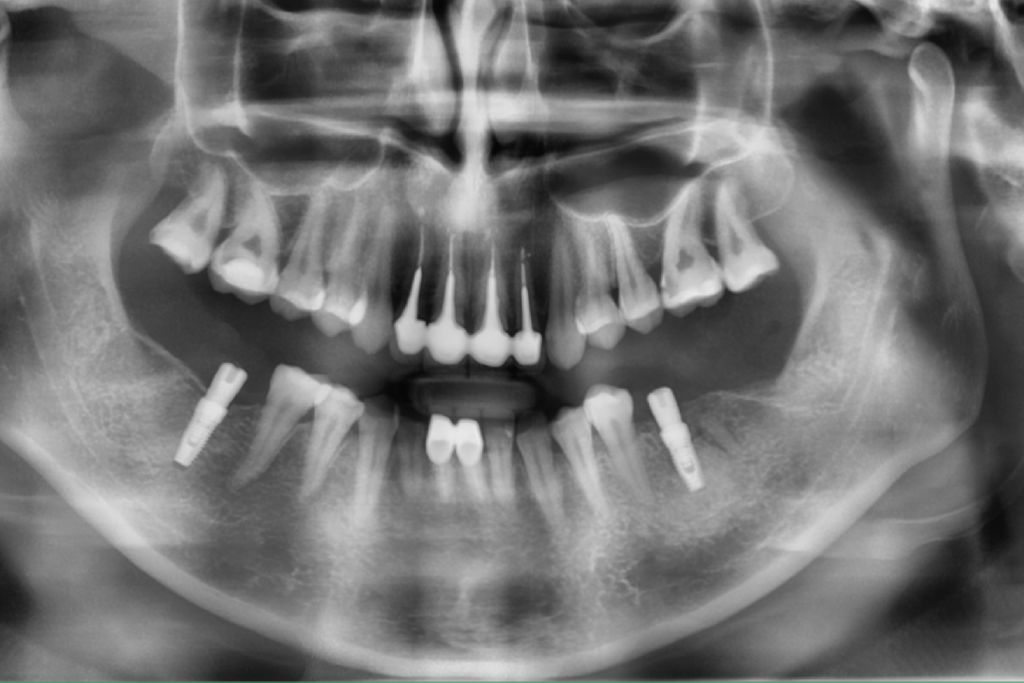

Описание клинического случая:

Клинический случай Узденовой Зульфы Альбертовны